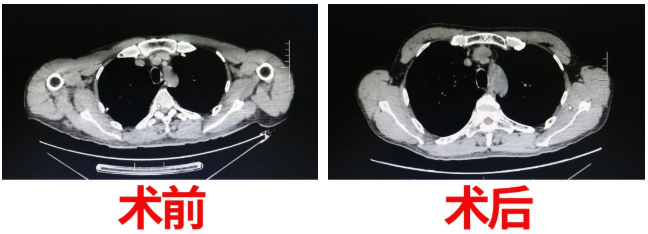

術前,胸外科醫(yī)護人員多次對該患者進行心理疏導,解除患者疑慮。經(jīng)過了縝密的術前準備后,于5月27日,在麻醉科及手術室的完美配合下,周鋼院長對該患者成功的實施了手術治療。由于患者胸腺瘤與心臟大血管侵及生長粘連緊密,術中手術難度極大,經(jīng)驗豐富的周院長僅用了不到1小時的時間,經(jīng)劍突下2cm小切口及雙側肋弓下三個“鑰匙孔”,成功分離并完整切除胸腺瘤,完成了該例經(jīng)劍突下入路?微創(chuàng)技術難度含量較高的手術。

重癥肌無力的手術治療效果,是伴隨著患者的恢復慢慢改善的。在胸外科醫(yī)護團隊精心、周到的護理下,術后,患者眼肌無力癥狀立即消失,術前視物模糊、全身乏力等癥狀也得到了改善?;颊唛_心的向病友們炫耀:“真沒想到,這么大的手術,刀口才這么小,現(xiàn)在的技術真是好呀!”患者更是對醫(yī)護人員無微不至的照護所感動。